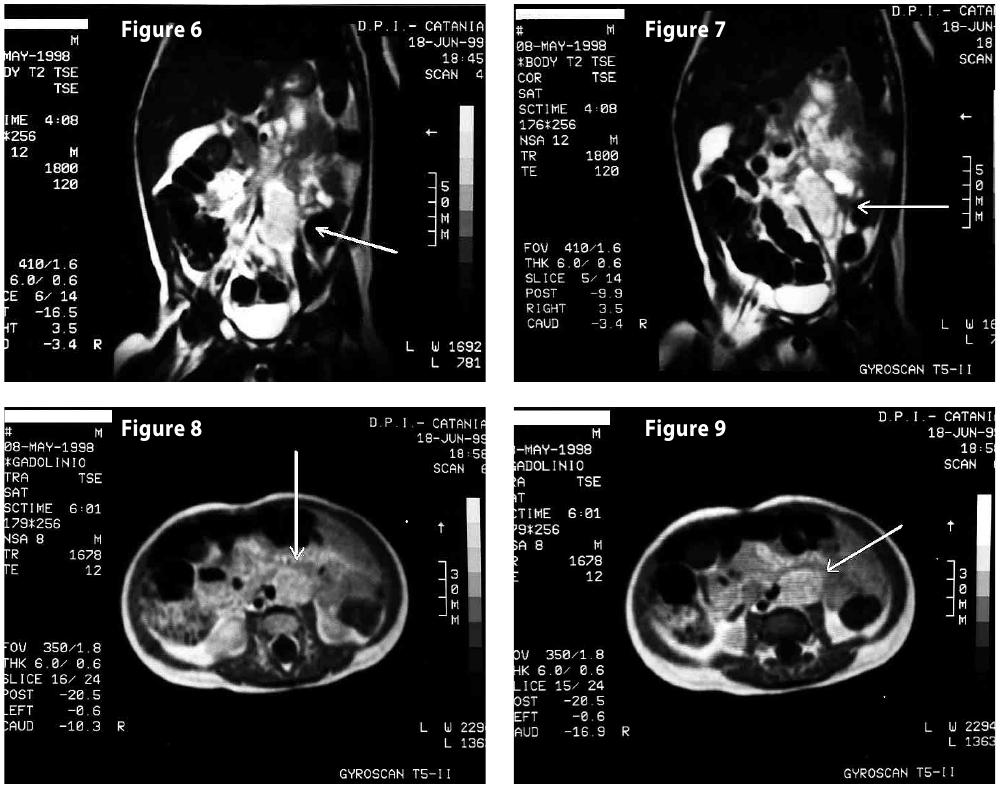

Figure6-7

Figure8-9

Figure6-7-8-9